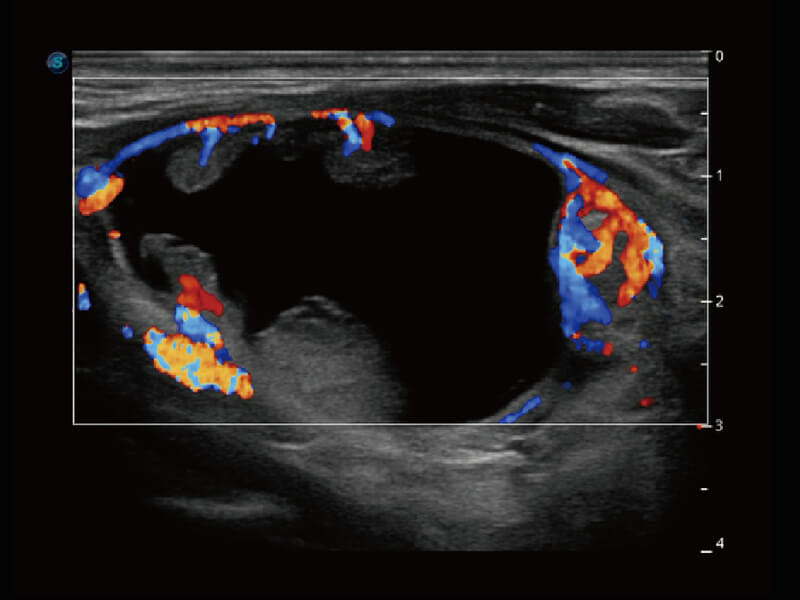

彩色多普勒超声诊断系统

S60探头工艺,从前端信号处理每一个环节采集无损声学数据,真实还原组织原貌,再现解剖细节。